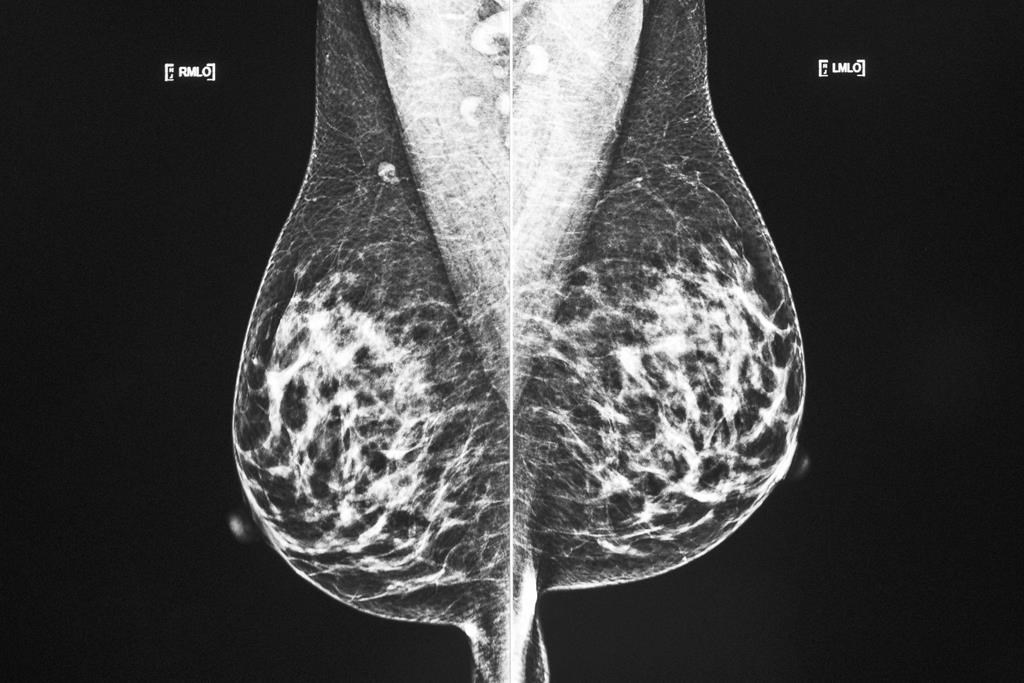

MONTRÉAL — Certaines patientes atteintes d'un cancer du sein ont maintenant l'option d'être soignées par cryoablation, grâce à une nouvelle technique que le Centre hospitalier de l'Université de Montréal est le premier au Québec à offrir.

La cryoablation consiste littéralement à «geler» la tumeur cancéreuse à l'aide d'une aiguille ultrafine. L'intervention, qui est pratiquée sous anesthésie locale, ne laisse pratiquement aucune cicatrice et la patiente reçoit habituellement son congé la journée même.

La cryoablation fonctionne le mieux pour les petites tumeurs qui font moins de 1,5 centimètre, a-t-il ajouté, ainsi qu'avec les tumeurs qui expriment des récepteurs hormonaux ou qui sont de plus bas grade.